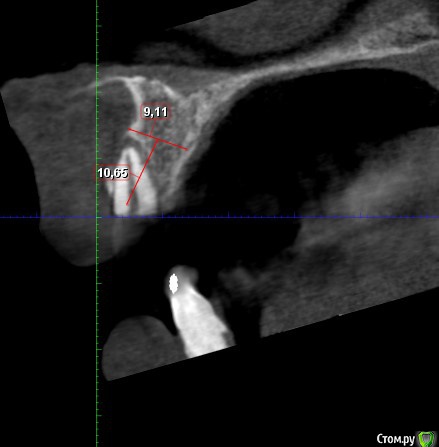

Дмитрий М Опубликовано 29 декабря, 2018 Поделиться Опубликовано 29 декабря, 2018 (изменено) Техник сделает восковой прогноз. И С него сделает шаблон. Больше для подстраховкипокажите пожалуйста фото шаблона и на КТ ширина гребня 9,11мм? срезы корректно выставлены? Изменено 29 декабря, 2018 пользователем Дмитрий М Ссылка на комментарий

bogdan_r Опубликовано 29 декабря, 2018 Автор Поделиться Опубликовано 29 декабря, 2018 (изменено) покажите пожалуйста фото шаблона и на КТ ширина гребня 9,11мм? срезы корректно выставлены?Шаблон будет после нг. Позиция импланта будет немного другая. Ширина в самом узком месте 9.11мм Изменено 29 декабря, 2018 пользователем bogdan_r Ссылка на комментарий